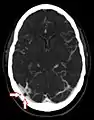

Arachnoid granulations seen on autopsy, where the dura mater has been removed but the arachnoid mater is left in place.